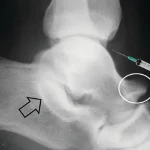

پس از آماده سازی، پزشک با استفاده از سوزن مخصوص و تحت هدایت تصویربرداری مانند فلوروسکوپی، مقدار مشخصی ماده حاجب را به درون مفصل تزریق میکند و این ماده باعث میشود جزئیات بافت های داخلی مفصل از جمله رباط ها، تاندون ها، غضروف ها و کپسول مفصلی با وضوح بیشتری در تصاویر مشخص میشوند و در برخی موارد ترکیبی از داروی بیحسی یا ضدالتهاب نیز تزریق میشود.